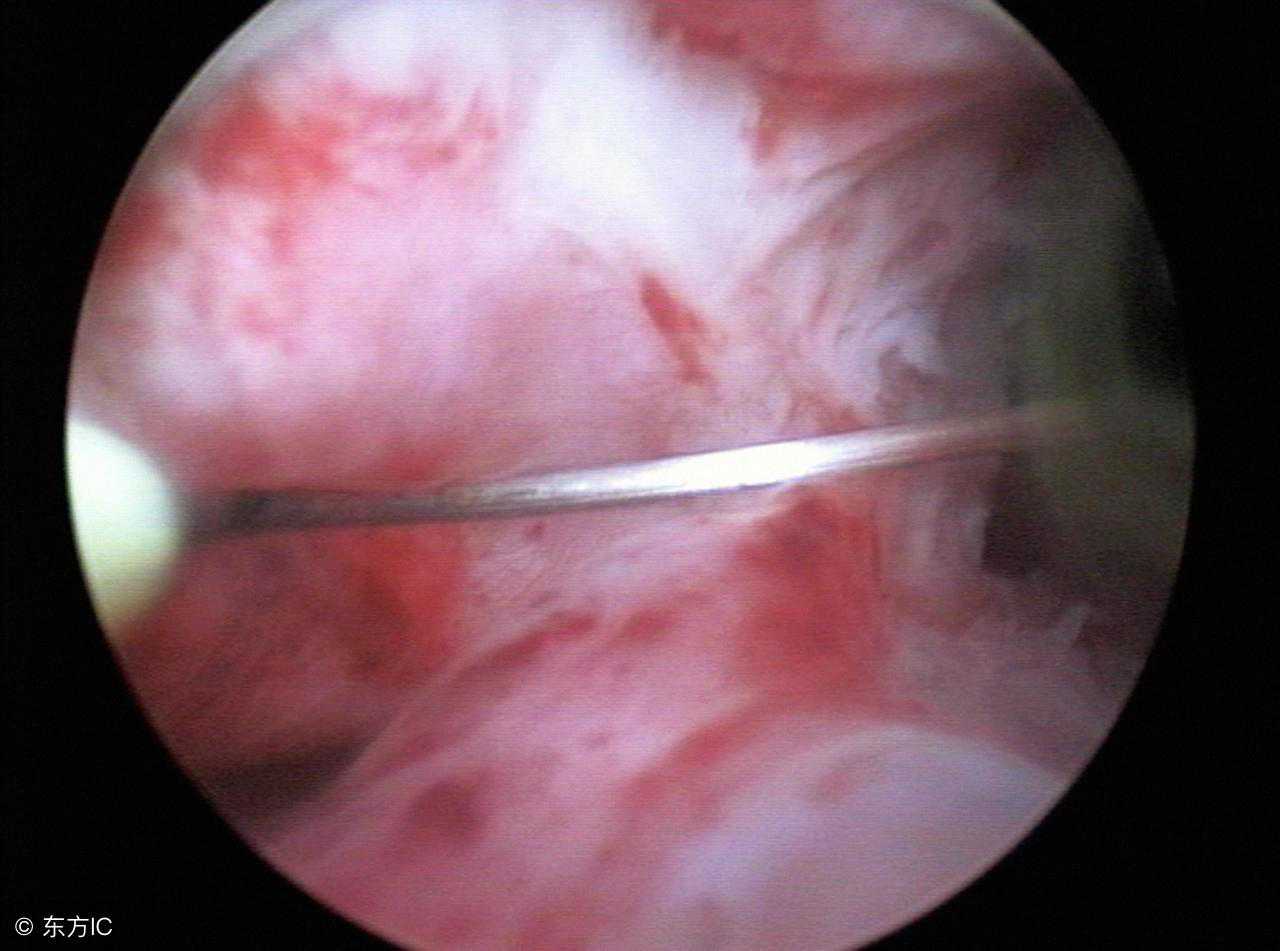

宫腔积液又称子宫积液,在临床上的发病率并不高。很多人不知道的是,不同年龄的子宫积液患者可由不同的原因所导致,需要区分生理性积液和病理性积液。

然后是积液的性质:如果是由输卵管,子宫内膜,宫颈炎急性炎症导致的就是淡黄色或者脓性积液;如果是以上三个部位癌性的,有可能是血性的;如果是异物,物理性炎症,可能就是淡黄色分泌物;如果是妊娠组织物残留,与残留大小相关,一般情况下可能会出现阴道点滴出血不干净,也有的人没有症状;正常宫腔是前后贴合的,宫腔操作后或者产后子宫复旧不良,子宫平滑肌收缩功能欠佳,可能出现宫腔积液。

还有绝经后子宫内膜萎缩,子宫萎缩,无症状宫腔积液等,以及其他比较少见的原因。